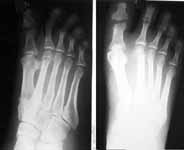

HISTORY: 25 year old engineer presented with a swelling right foot in the region of 2nd MTP joint. He noticed this swelling about three months ago following which a POP cast was applied elsewhere presumably under the diagnosis of a fracture. On removal of cast the swelling was persisting and may be was a bit more prominent. He gives h/o multiple ulcers in both the feet for which a diagnosis of trophic ulcers were made.

His younger brother was diagnosed to have "Genetic neuropathy" when he developed trophic ulcers. This brother subsequently developed a similar swelling which was finally diagnosed (after the initial diagnosis of fracture) to be a calcified chondroma and a second toe ray amputation was done few years ago. He subsequently lost first toe on the same foot following trophic ulcers. Strong family history of consanguinity in the parents. I am attaching three serial X rays of lastfour months. Is it a tumour around 2nd metatarsal or is it a healing stress fracture?? Thanks in advance.

Aug 2003

Oct 2003

Looking at the sequential radiographs, I would say this is a healing fracture. The question is whether there is something going on that predisposed the metatarsal to fracture (i.e., tumor, infection, neuropathy,etc.). I would initiate vascular workup (arterial and venous), infection workup (CBC with differential, ESR, C-reactive protein),diabetes mellitus/neuropathy workup and follow the fracture healing. At some point an MRI may be helpful, but at this point you'll just see a large reactive zone (inflammation) due to the fracture healing and I doubt it would help narrow the diagnostic possibilities. I'm sure there is better advice out there. Good Luck!

I think its a healing fracture but the history just does not add up right.